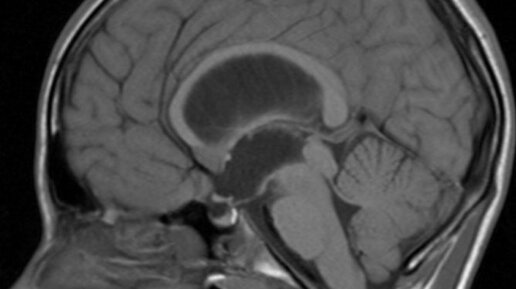

Гидроцефалия